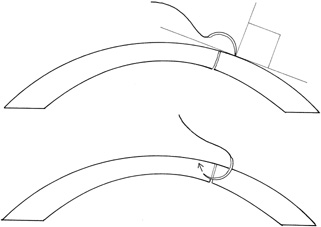

The goals in treating partial thickness corneal lacerations include preventing infection and promoting re-epithelialization and stromal healing. Every effort is made to minimize scarring and surface irregularity. If the wound edges are in good apposition with no wound gape, pressure patching with the use of prophylactic topical antibiotics is sufficient. Re-epithelialization is usually rapid. If the wound is unstable, a bandage soft contact lens may be used to support the wound and encourage re-epithelialization by minimizing the traumatic effect of lid movement (Fig. 2). Topical antibiotic prophylaxis, as well as cycloplegia for comfort, is used while the lens is in place. The lens should remain in place until wound healing is stable and complete re-epithelialization has occurred.

BANDAGE SOFT CONTACT LENS.

For small, self-sealing corneal perforations, a bandage contact lens may be sufficient to protect and support the wound as it heals. Such lacerations include nondisplaced, beveled, self-sealing wounds. If aqueous leakage persists for more than 24 hours or there is progressive shallowing of the anterior chamber, more definitive treatment should be undertaken. Treatment with a bandage contact lens in children should be done only with extreme caution and close follow-up care.

In cases that respond satisfactorily, the contact lens should be kept in place until the wound has stabilized (usually 3–6 weeks). A protective shield should be worn at all times. Topical antibiotic prophylaxis and cycloplegia are recommended with the lens in place.